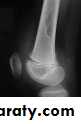

O/E vague swelling at the bone end and signs of joint irritation.X-ray:

Rarefied area of the bone end reaching just below the articular surface.Eccentric lesion with bone expansion and ballooning with cortical thinning, sometimes pathological fracture.

There may be calcific trabiculations inside the lesion giving it the commonly known saop-bubble appearance.